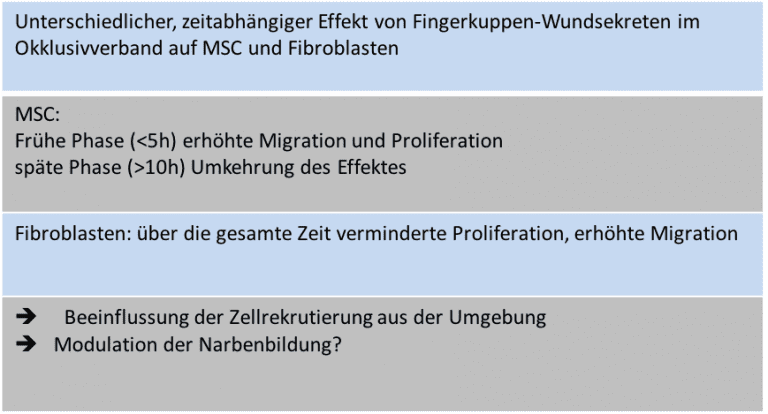

Einfluss von Wundsekreten aus Okklusivverbänden auf Mesenchymale Stammzellen

Projektleiter: Dr. med. univ. Michael Cerny

Fingerkuppenverletzungen sind häufig und können oft mittels Okklusivverbänden konservativ zur Abheilung gebracht werden. Die Wunden heilen dabei praktisch narbenlos ab und es kommt i.d.R. zu ästhetisch und funktionell sehr guten Ergebnissen. Spalthautentnahmestellen können ebenso behandelt werden um die Wundheilung zu verbessern. Da mesenchymale Stammzellen (MSC) wichtige Modulatoren der Wundheilung sind, haben wir die Hypothese aufgestellt, dass die Wundsekrete von Fingerkuppenverletzungen und Spalthautentnahmestellen im Vergleich zu Serum derselben Patienten die Proliferation und Migration von MSCs beeinflusst.

Wir zeigen hier einen starken, zeitabhängigen Effekt von Wundsekreten auf Migration und Proliferation von Mesenchymalen Stammzellen. Mesenchymale Stammzellen sind wesentlich an der Bildung des Granulationsgewebes in der Wundheilung beteiligt und spielen eine Rolle bei der Bildung von Narbengewebe. Die frühe Aktivierung der Migration von MSCs in der Wundheilung könnte über eine frühe, relative Erhöhung der MSCs im heilenden Gewebe die Narbenbildung modulieren und damit zu den beobachteten sehr guten Ergebnissen bei Fingerkuppenverletzungen beitragen.